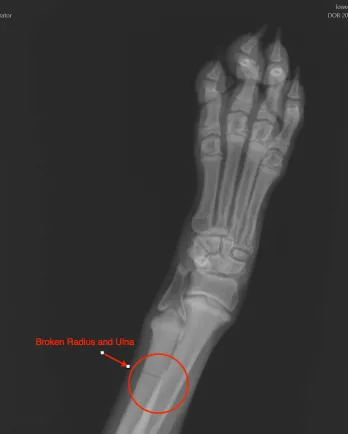

Just this week in my practice a five-month old boxer puppy named Caleigh came in partially weight-bearing on her left front leg. Her dad told me that she started limping over the weekend, and he had no idea why. She never cried or complained. He never saw any kind of accident or trauma. She even took a four-hour car ride with him to visit his children in Boston without a complaint. When I examined Caleigh my only finding was that she had heat coming from the left front carpus (wrist), and when I pressed on the joint she tried to move away from me. She never cried once during my exam. My obvious next step was to take an x-ray of her leg. To my surprise I found that she had a complete fracture of both the radius and ulna. Thankfully, Caleigh will be fine. The bone was not displaced, so I splinted the leg, immobilizing the joints above and below, and sent her home with pain medications and an appointment in two weeks for a cast change.

In acute, extreme situations such as Caleigh’s in which she actually had a broken bone, our rational minds come to accept that yes Caleigh must be in pain. If you have ever broken any bones, you know this hurts BIG TIME! Yet Caleigh never cried once.